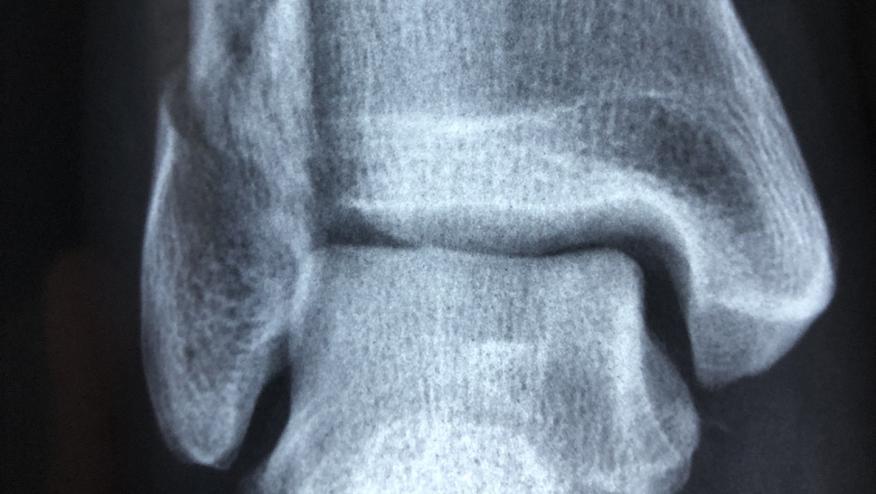

This randomized clinical trial was done at 6 sites in the Netherlands and included 100 ankle OA patients, with VAS pain > 40 (0-100 scale) and imaging evidence of tibiotalar joint space narrowing. Patients were randomized to receive ultrasonography-guided intra-articular injections of either PRP (n = 48) or placebo (saline; n = 52) and studied over 26 weeks. The primary outcome measure was the American Orthopaedic Foot and Ankle Society score (range, 0-100; higher scores indicate less pain and better function) over 26 weeks.

Approximately 3.4% of adults have ankle (tibiotalar) OA, with ankle OA being more common than hip/knee OA in younger patients; for whom a nonsurgical intervention would be advantageous.